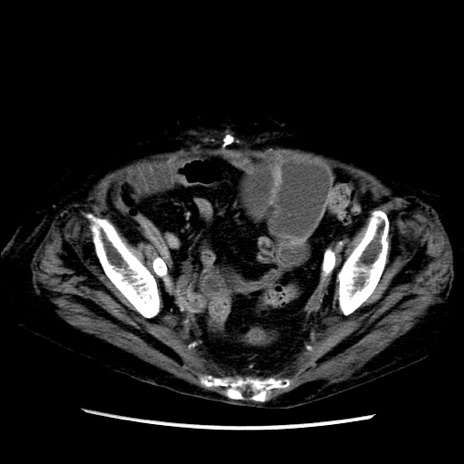

症例14(横断像)

【症例】 90歳代女性

【主訴】 腹痛・嘔吐

【現病歴】今朝から左側腹部痛を認めた。 経過観察していたが、嘔吐を認めたため来院。

【既往歴】 子宮癌術後

【身体所見】 意識清明、BP 127/54mmHg、P 98bpm Sp02 95%(RA)、BT 35.8°C、腹部平坦・軟腸ぜん動音聴取良好、右下腹部圧痛(+) 反跳痛なし

【データ】WBC 9800、CRP 0.46